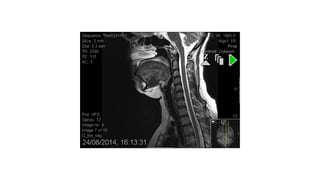

Spinal Lesions

cord lesion